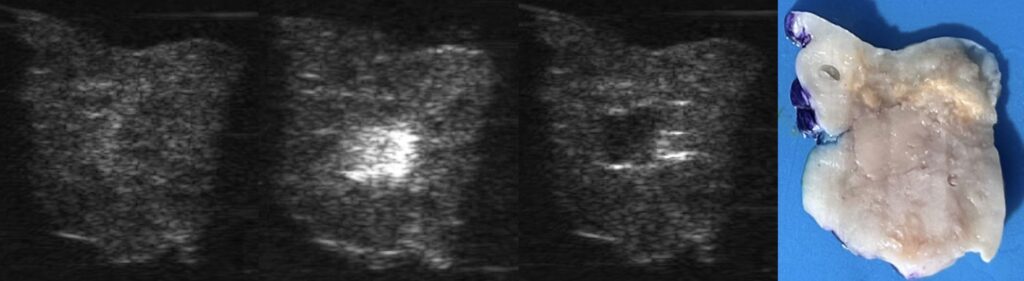

- possibility of real-time visualization via conventional, more accessible than MRI, diagnostic ultrasound imaging:

- vapor bubbles formed during histotripsy strongly scatter ultrasound and appear hyperechoic (bright) on ultrasound;

- the resulting liquefied tissue lacks ultrasound scatterers and appears hypoechoic (dark) on ultrasound;